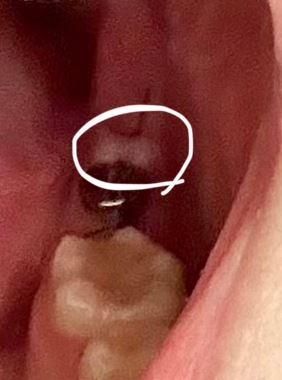

임플란트 시술 일주일 후 시술 부위 근처에 하얀 잇몸이 있어요

뼈 이식 조금 했고 하얗게 올라온 부분이 절개되었던 곳이긴 한데

통증, 냄새는 없어요

찾아보니 염증은 아니고 낫고 있는 거라고 하긴 하는데 맞나요?

지금 시술 후 8일 경과됐습니다

• 1번 째 사진

사진에 보이는건 염증은 아니고 잇몸이 눌려서 생긴 일시적인 현상입니다. 크게 걱정하지 않으셔도 될것같습니다.

시술 후 8일 차라면 조금 더 지켜봐야 하며 사진 상으론 잇몸의 염증반응으로 보이진 않습니다.

잇몸이 아무는 과정에서 하얗게 보이는 경우가 있습니다 문제가 되지는 않을것으로 생각됩니다.

자세한 확인을 위해서 치과에서 진료를 받아보는 것을 권유드립니다.